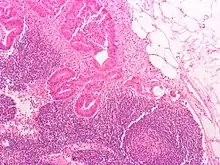

Definitive staging can only be done after surgery and histopathology of colorectal carcinoma. An exception to this principle would be after a colonoscopic polypectomy of a malignant pedunculated polyp with minimal invasion. Preoperative staging of rectal cancers may be done with endoscopic ultrasound. Adjunct staging of metastasis include abdominal ultrasound, MRI, CT, PET scanning, and other imaging studies.

Dukes classification

In 1932 the British pathologist Cuthbert Dukes (1890–1977) devised a classification system for colorectal cancer.[3] Several different forms of the Dukes classification were developed.[4][5] However, this system has largely been replaced by the more detailed TNM staging system and is no longer recommended for use in clinical practice.[6]